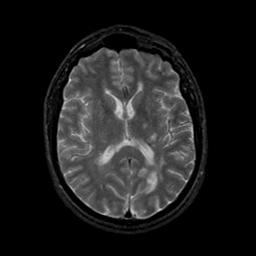

MR Study #9, April 14, 1991 -- Slice #28